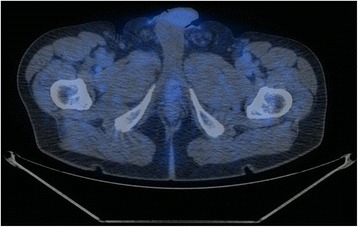

Fig. 3.

False positive case (PET/CT axial scan). This scan shows a mild focal uptake of 11C–choline localized in the BUJ along midline